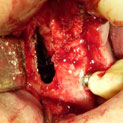

Procedimiento: se realiza una incisión en la encía, se aborda el hueso maxilar superior realizando una pequeña apertura en el margen externo del maxilar, y se introduce un cemento formado por el propio hueso y sangre del paciente, y un material óseo conductor, que proporciona una serie de condiciones básicas para la formación de hueso.

Una vez realizada la intervención, en algunos casos se pueden colocar los implantes a la misma vez y en otros, es necesario esperar seis meses para que el material óseo forme un hueso con buena calidad que asegure el éxito de los implantes.